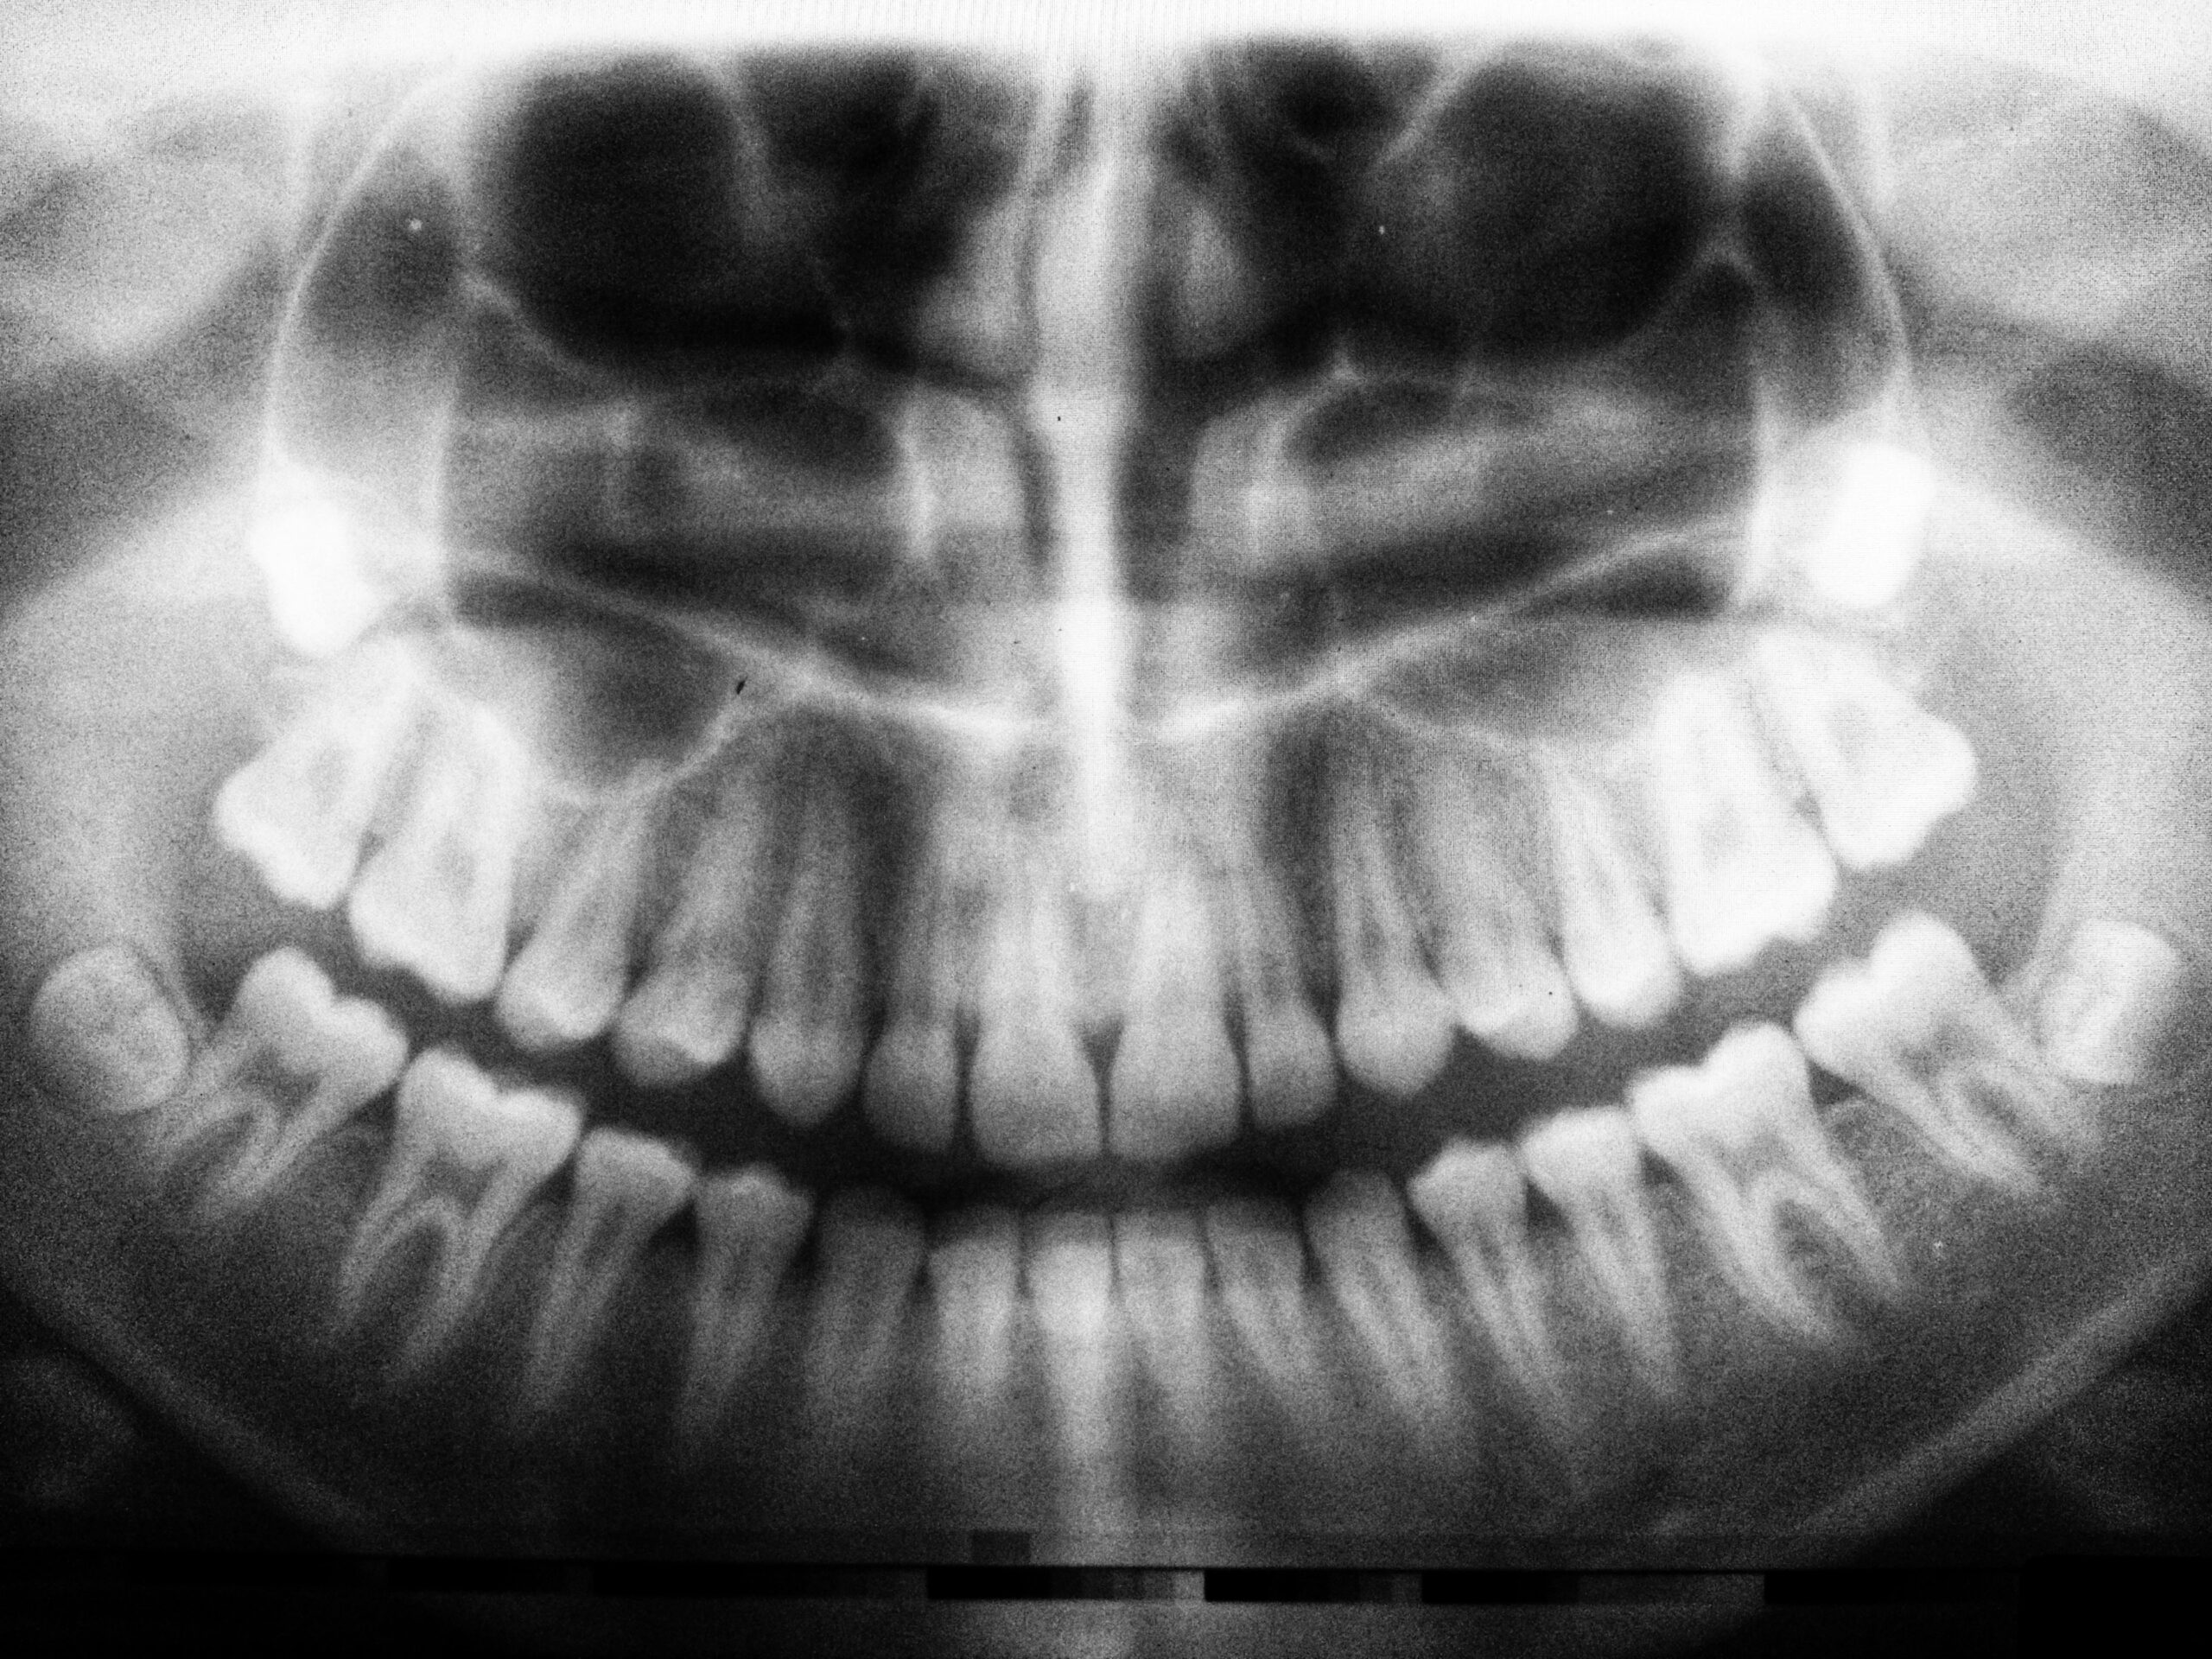

Dental exams and panoramic or 3D imaging help show where a wisdom tooth sits, how the roots form, and whether nearby nerves or sinus spaces are close. With that information, your dentist can outline options such as continued monitoring, timing eruption‑window checks, or discussing removal if risks rise. If extraction is recommended, you can read more about the steps and healing on our page about wisdom tooth removal.

Other signs include headaches that start near the jaw joint, ear-area discomfort, or pain that worsens when clenching. If you develop facial swelling, fever, difficulty swallowing, or you cannot open your mouth well, seek urgent dental or medical care. Dentists confirm the position of wisdom teeth with panoramic X‑rays; when nerves or sinus spaces are close, a focused 3D scan (CBCT) may be used to map the area and plan care safely [6].

See a dentist if you have pain, swelling, a bad taste, or trouble cleaning the area behind your last molar. You should also schedule a check if your gums get sore on and off near a partly emerged wisdom tooth, or if biting on the second‑to‑last tooth feels sensitive. Teens and young adults should ask for an exam and panoramic X‑ray even without pain, because early monitoring can spot tight space or risky angulation before problems start. If you’re unsure why wisdom teeth are impacted in your case, a focused evaluation can explain your options.

Even without symptoms, plan a review during the late teen years, after braces or aligners, before long travel or deployment, or if you have a health change that may affect healing. Your dentist will assess space behind the second molars, tooth angulation, root development, and proximity to nerves or the sinus on imaging. Based on those findings, you may continue with periodic monitoring, be given home‑care tips to keep the area clean, or be referred to discuss timing for removal if risks rise.